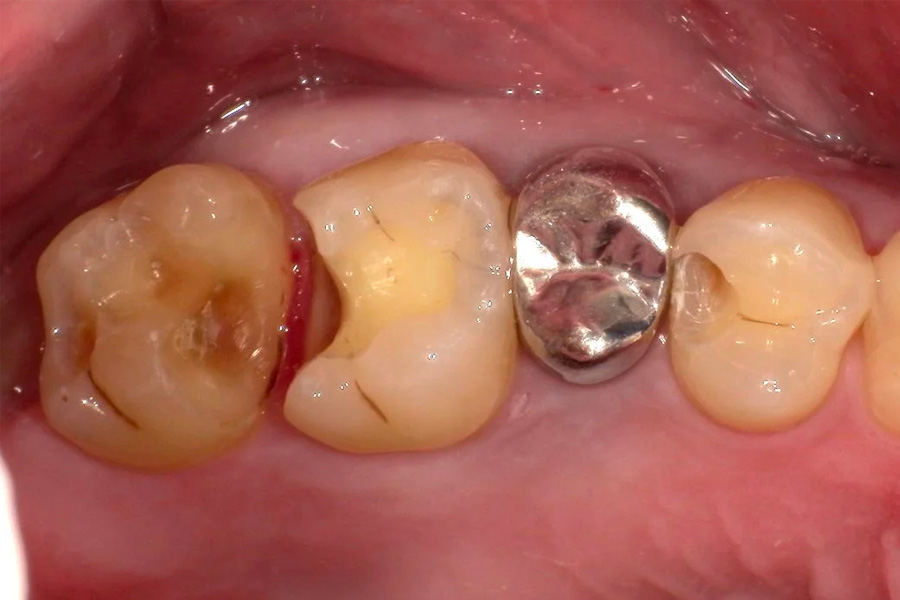

治療後

治療中

(虫歯除去後)

治療内容 右上4.5.6番目の虫歯を除去し、セラミックインレーを装着しました。

治療に伴うリスク 神経を温存しています。一時的に知覚過敏の症状がでることがあります。

また、咬合の強い方の場合材料の破折の恐れがあり、夜間のマウスピースの装着をお勧めしております。